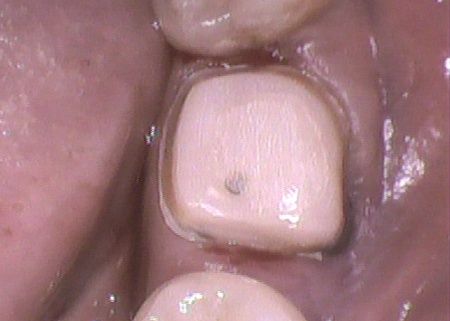

治療後

次に、被せ物を装着できるよう土台の形を整えて型取りを行い、被せ物を作製します。

最後に、完成したジルコニアクラウンを装着し、噛み合わせに問題がないことを確認して治療を終了しました。